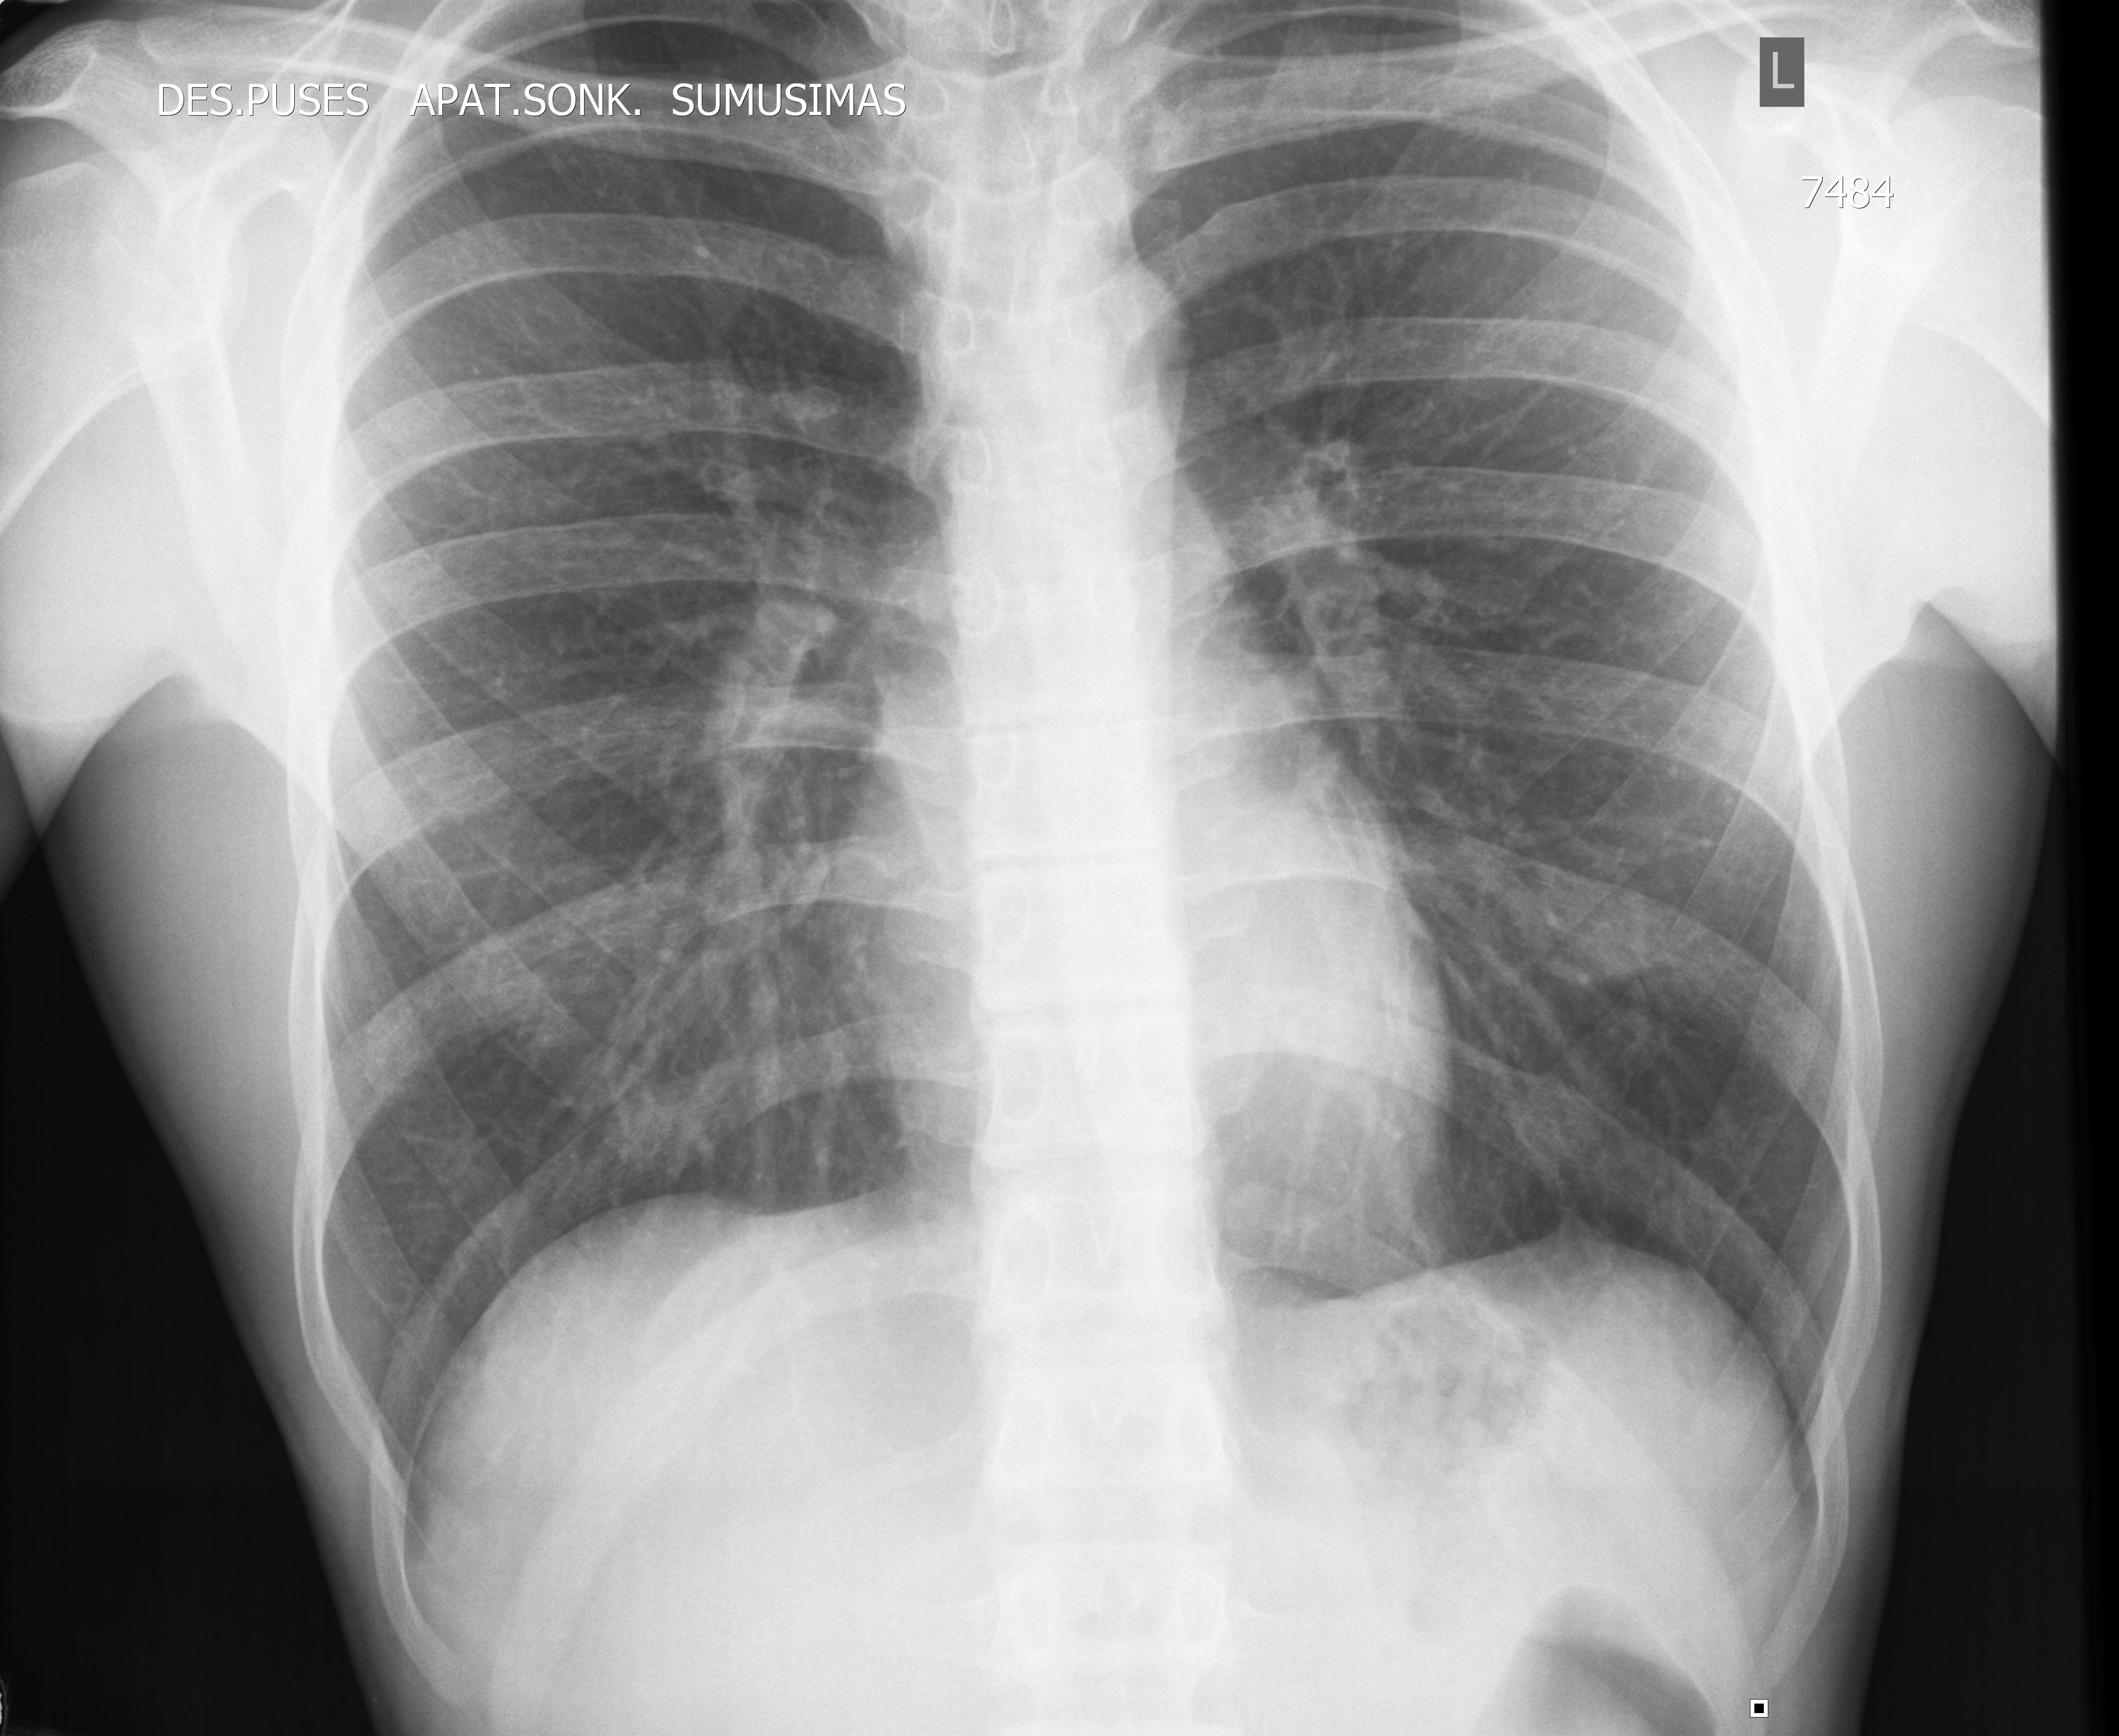

19y M

Rgdwdwdjh2.jpg